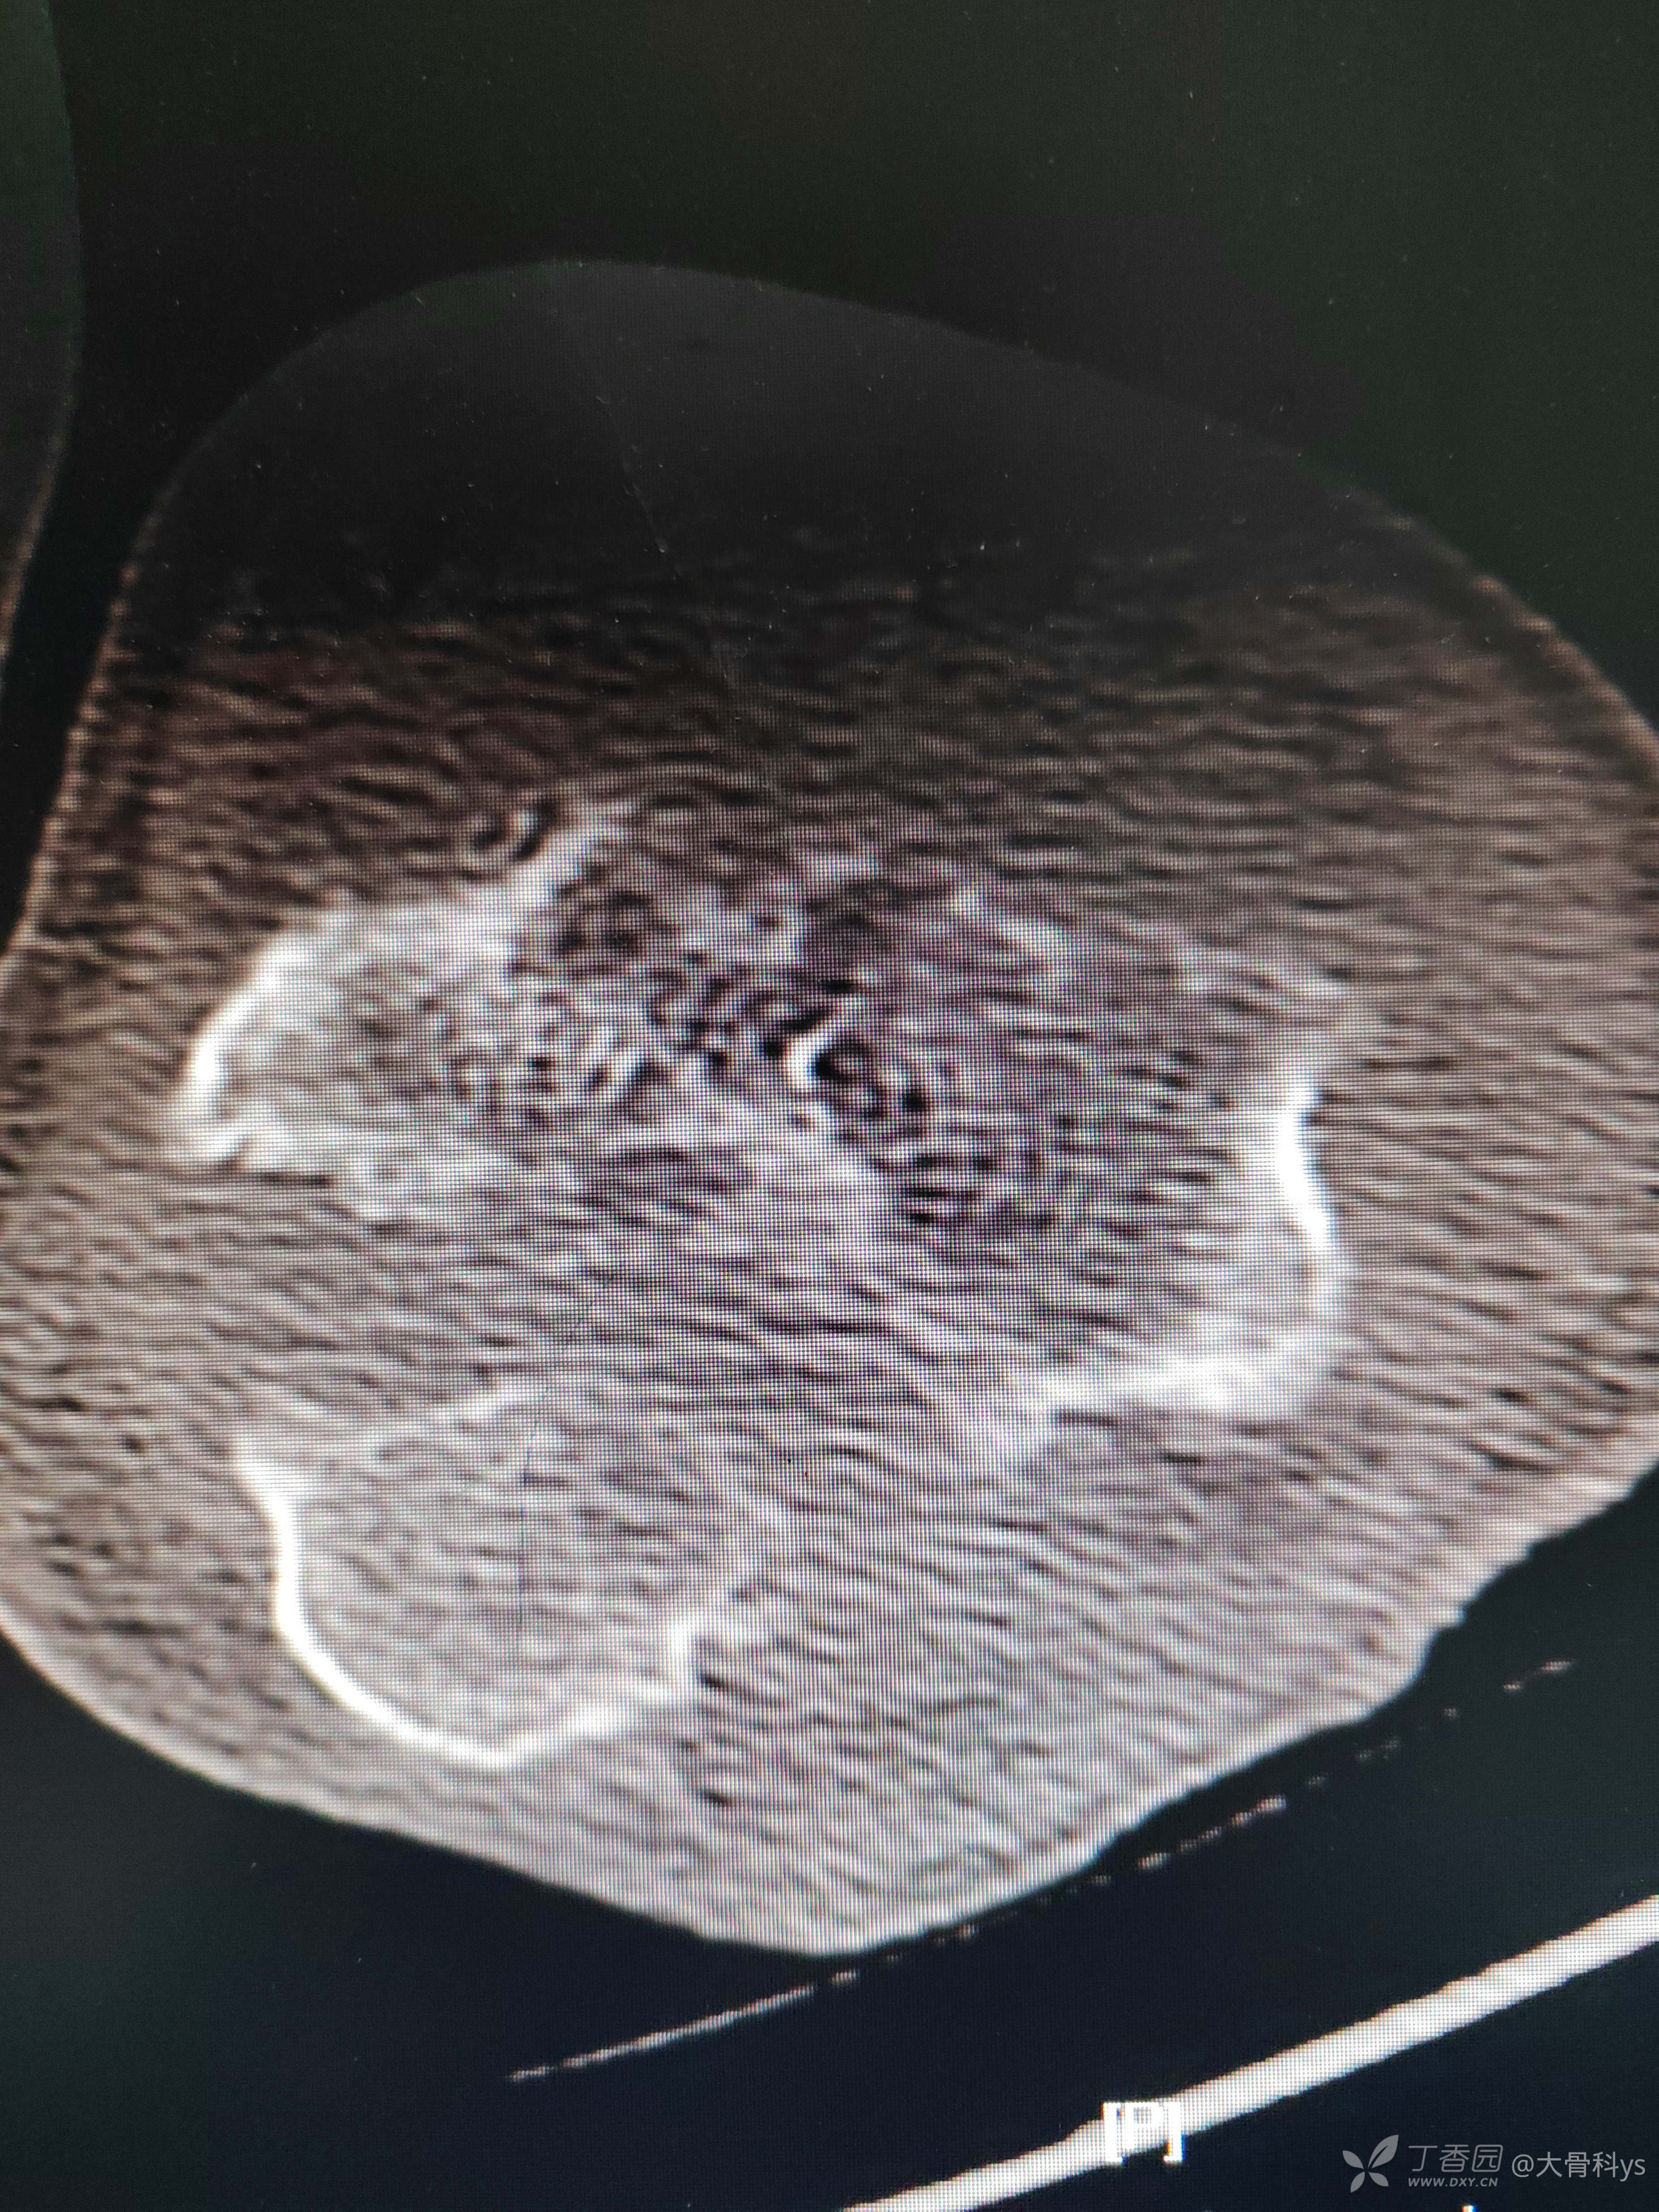

影像学资料

考虑肘关节结核,行关节腔清理+骨髓炎病灶清除+负压封闭引流术。病灶组织再次培养,病灶组织结核杆菌培养,找抗酸杆菌,结核杆菌核酸及利福平耐药检测结果暂未回报。

3、骨髓炎病灶清除后因大量骨质缺损,关节周围软组织已清理,后期肘关节如何重建?